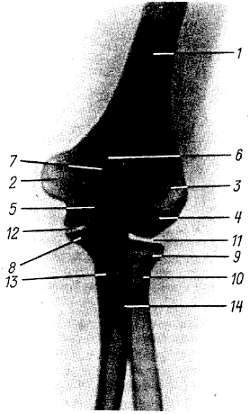

На рентгенограммах области локтевого сустава (рис. 45) получается одновременное изображение дистального отдела плечевой кости и проксимальных отделов костей предплечья.

Рис. 45. Рентгенограмма локтевого сустава женщины 25 лет; задняя проекция.

1 - диафиз плечевой кости; 2 - медиальный надмышелок; 3 - латеральный надмыщелок; 4 - capitulum humeri; 5 - блок; 6 - локтевая ямка; 7 - локтевой отросток; 8 - венечный отросток локтевой кости; 9 - головка лучевой кости: 10 - шейка лучевой кости; 11 - плечелучевой сустав; 12 - плечелоктевой сустав; 13 - диафиз локтевой кости; 14 - бугристость лучевой кости.

На заднем и боковом снимках видны все описанные выше детали этих отделов. На боковом снимке tróchlea и capítulum húmeri наслаиваются друг на друга, вследствие чего тени этих образований имеют вид концентрических кругов. Хорошо видны "рентгеновские суставные щели" articulátio humeroulnáris, articulátio humeroradiális, art. radioulnáris proximalis.

На задней рентгенограмме особенно ясно заметна щель плечелучевого сустава, на боковом снимке прослеживается на всем протяжении щель плечелоктевого сустава.